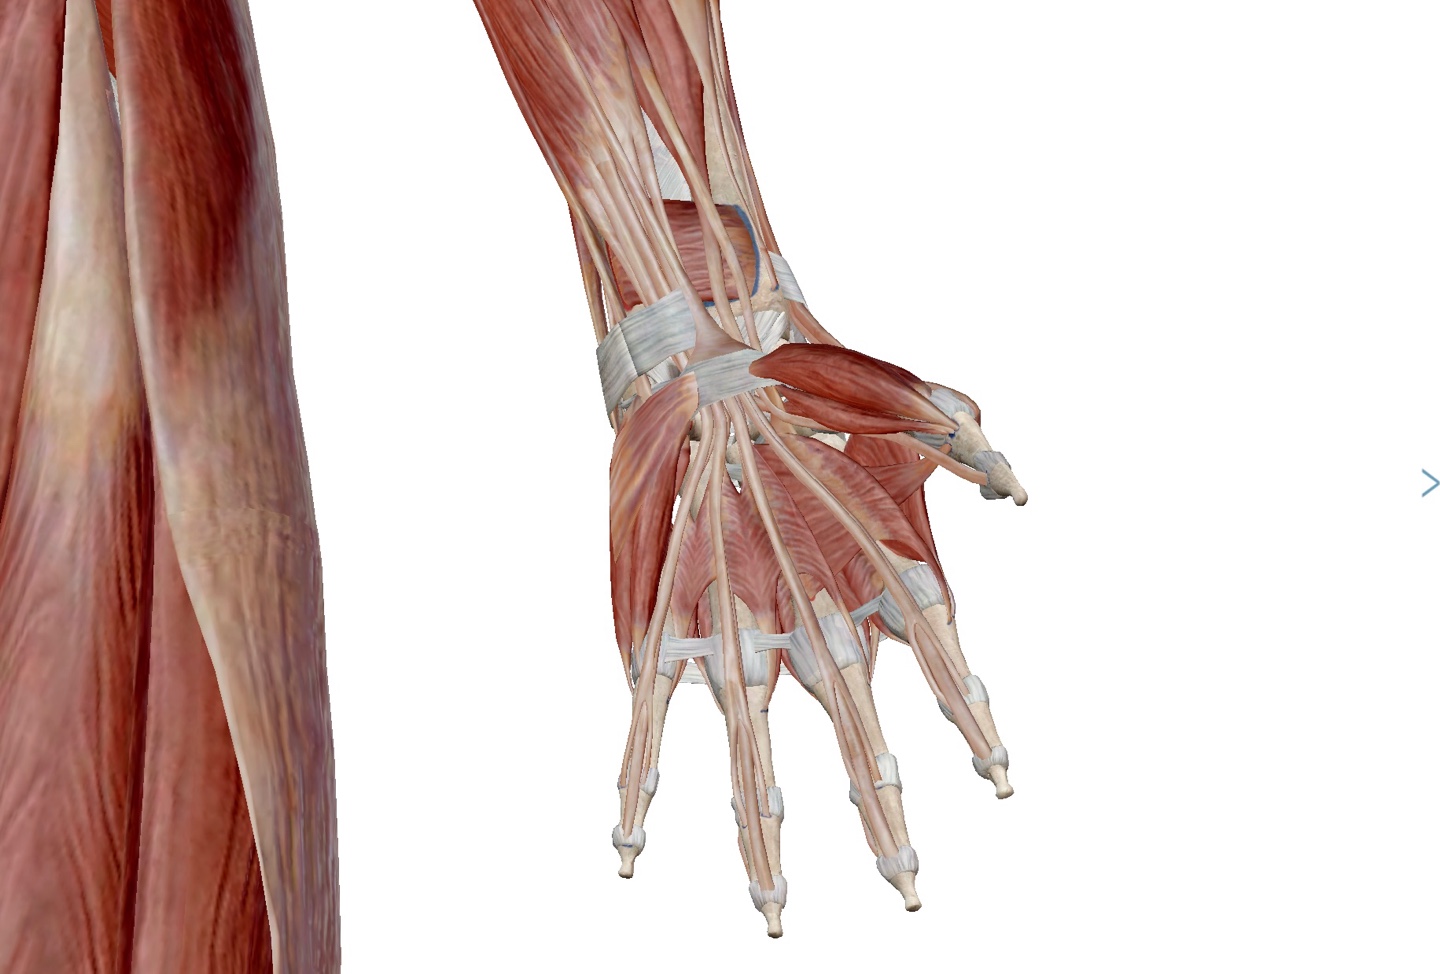

손바닥에서 무지구(Thenar)의 근육은 무지내전근(Adductor policis), 무지대립근(Opponens policis), 단무지굴근(Flexor policis brevis), 단무지외전근(Abductor policis brevis)이 있으며, 무지 기저부 신측의 해부학적 코담배갑(Anatomical snuff box)은 장무지외전근(Abductor policis longus), 장무지신근(Extensor policis longus), 단무지신근(Extensor policis brevis)

소지외전근 : Abductor digiti minimi

소지굴근 : Flexor digiti minimi

충양근 : Lumbricalis

소지대립근 : Opponens digiti minimi

횡수근 인대 : Transvers carpal ligament

무지내전근(횡두) : Adductor policis (Transvers head)

무지내전근(사두) : Adductor policis (Oblique head)

단무지굴근 : Flexor policis brevis

단무지외전근 : Abductor policis brevis

무지대립근 : Opponens policis

지신근 : Extensor digitorum

배측골간극 : Dorsal interosseous

장무지신근 : Extensor policis longus

단무지신근 : Extensro policis brevis

장무지외전근 : Abductor policis longus

시지신근 : Extensor indicis